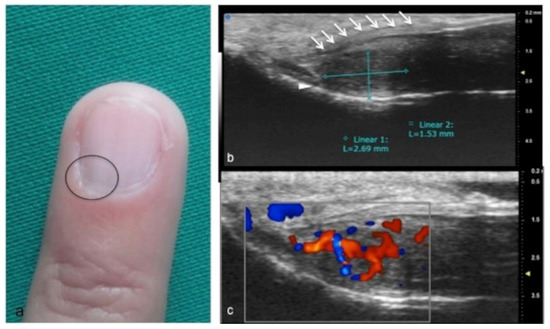

Figure 1.

Sagittal view of A1 pulley (white arrows) presenting as a fusiform structure with a hypo-echoic signal contoured by a thin hyperechoic line. The superficial flexor tendon is visible (square parenthesis).

Figure 11.

Glomus tumor. The location corresponds to the pulp of finger IV (a). The patient had the classical triad of symptoms: paroxysmal pain, pinpoint pain, and cold hypersensitivity, lasting for two years. In (b), UHFUS shows a well-delimited nodule in contact with the adjacent phalangeal bone (arrowhead), but no cortical deformity is present. No significant hyperemia on color Doppler was noticed. On CUS (c), the nodule was delineated only thanks to the help of the preliminary UHFUS exam.

Figure 12.

Glomus tumor in the subungual space. No clear alterations were visible during clinical examination at the site of pain (circle in (a)). In (b), UHFUS effectively demonstrates the presence of a hypo-isoechogenic nodule (calibers) in contact with the adjacent phalangeal bone (arrowhead) under the nail plate (arrows). Note the small deformation of the nail plate. Mild vascularization on color Doppler was present (c).

Glomus tumors are rare, benign, vascular neoplasms arising from the glomus body, which is a contractile neuromyoarterial structure found in the reticular dermis. This structure controls blood pressure and temperature by regulating blood flow in the cutaneous vasculature. Hyperplasia in any of these parts can lead to tumor formation, which is extremely painful. Glomus tumors account for 1–5% of soft-tissue tumors of the hand, and 75% of them are subungual in location. Other less commonly involved sites in the hand are the nail matrix, nail bed, and pulp of the finger. The delay in diagnosing these tumors for many years is a significant problem. It is not uncommon that patients are easily misdiagnosed with conditions such as neuropathic complaints, arthritis, or neuralgia and undergo unsuitable treatment. For these reasons, when the clinical examination is equivocal, noninvasive imaging techniques may be needed to aid in the diagnosis and delineate the anatomy preoperatively. Complete surgical excision of the tumor is the only effective treatment. Incomplete excision is considered the main cause of recurrence. US follow-up and/or intraoperative US may be useful for reducing recurrence and ensuring adequate resection, and the UHFUS tool is promising in this field [56].